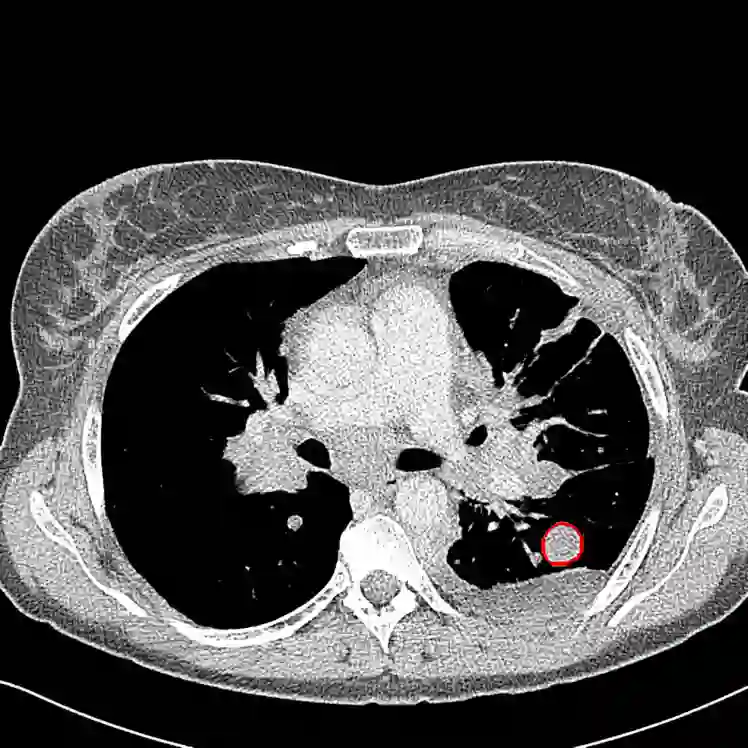

Radiomics uses quantitative medical imaging features to predict clinical outcomes. Currently, in a new clinical application, finding the optimal radiomics method out of the wide range of available options has to be done manually through a heuristic trial-and-error process. In this study we propose a framework for automatically optimizing the construction of radiomics workflows per application. To this end, we formulate radiomics as a modular workflow and include a large collection of common algorithms for each component. To optimize the workflow per application, we employ automated machine learning using a random search and ensembling. We evaluate our method in twelve different clinical applications, resulting in the following area under the curves: 1) liposarcoma (0.83); 2) desmoid-type fibromatosis (0.82); 3) primary liver tumors (0.80); 4) gastrointestinal stromal tumors (0.77); 5) colorectal liver metastases (0.61); 6) melanoma metastases (0.45); 7) hepatocellular carcinoma (0.75); 8) mesenteric fibrosis (0.80); 9) prostate cancer (0.72); 10) glioma (0.71); 11) Alzheimer's disease (0.87); and 12) head and neck cancer (0.84). We show that our framework has a competitive performance compared human experts, outperforms a radiomics baseline, and performs similar or superior to Bayesian optimization and more advanced ensemble approaches. Concluding, our method fully automatically optimizes the construction of radiomics workflows, thereby streamlining the search for radiomics biomarkers in new applications. To facilitate reproducibility and future research, we publicly release six datasets, the software implementation of our framework, and the code to reproduce this study.